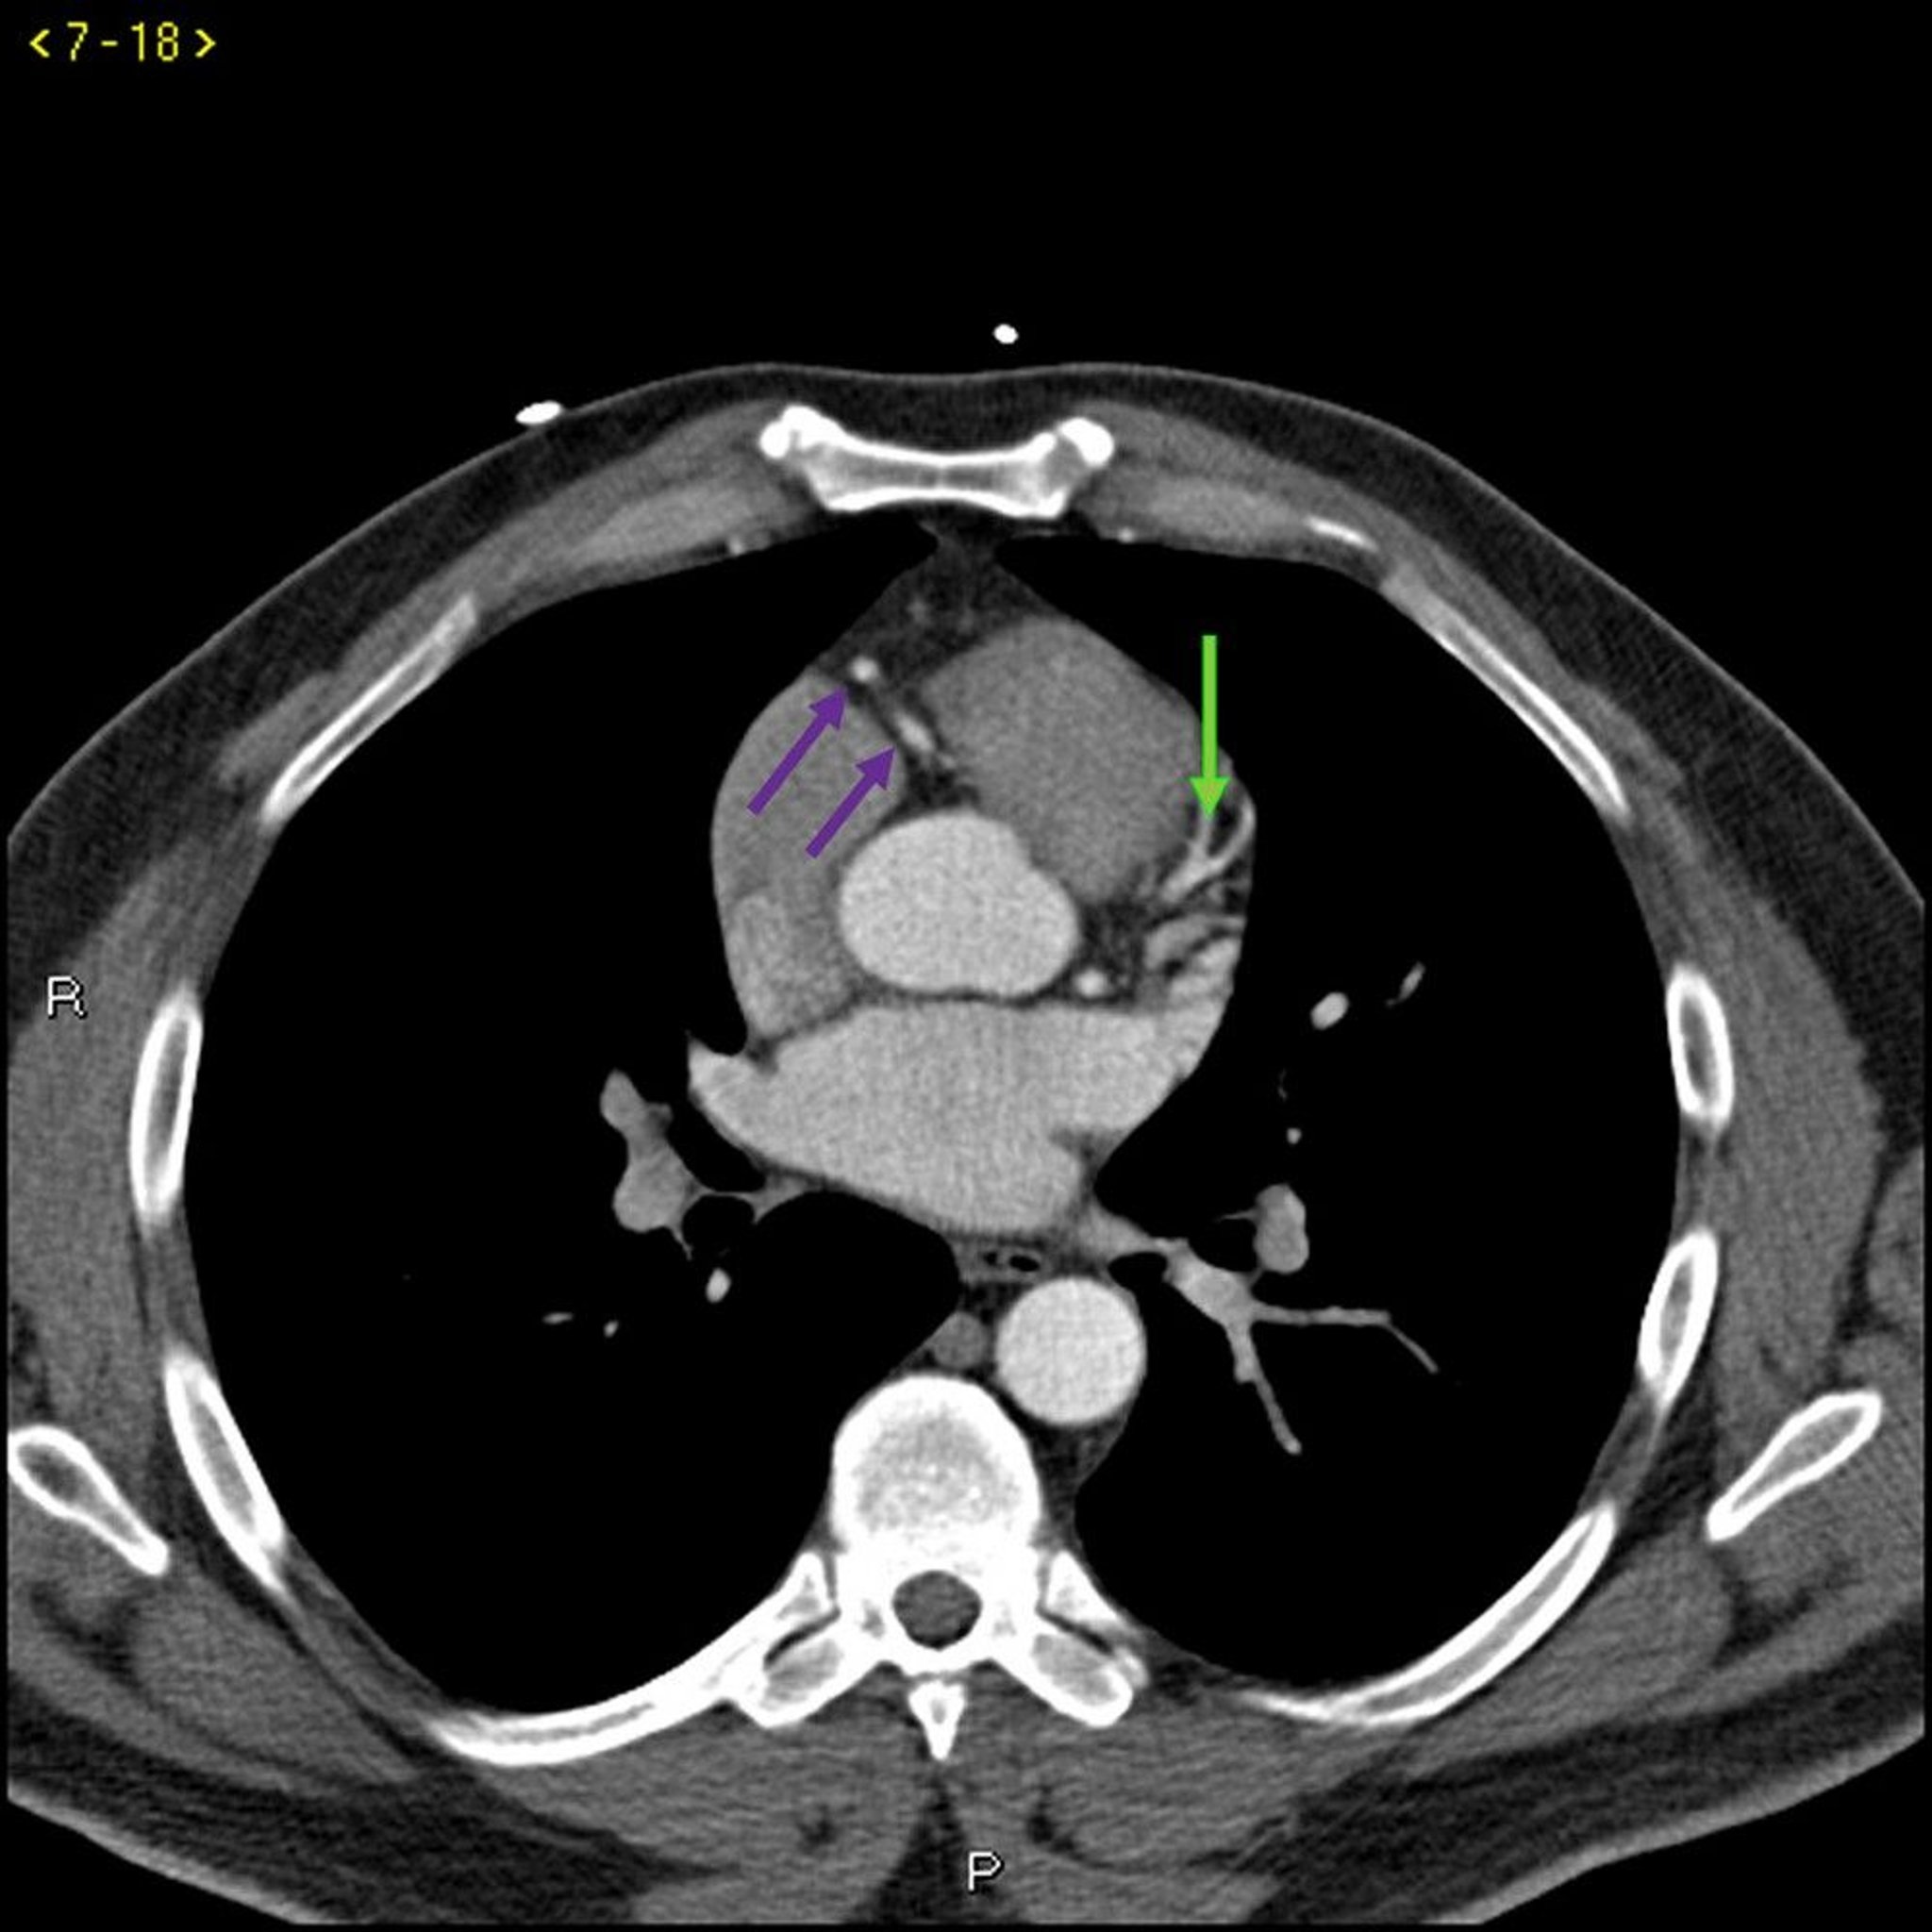

Contrast CT Showing Normal Coronary Arteries – Slide 3

This contrast CT shows normal coronary arteries. The left main is indicated by the red arrow. The left anterior descending and left circumflex arteries are indicated by the green and blue arrows respectively and the right coronary artery is indicated by the purple arrow.